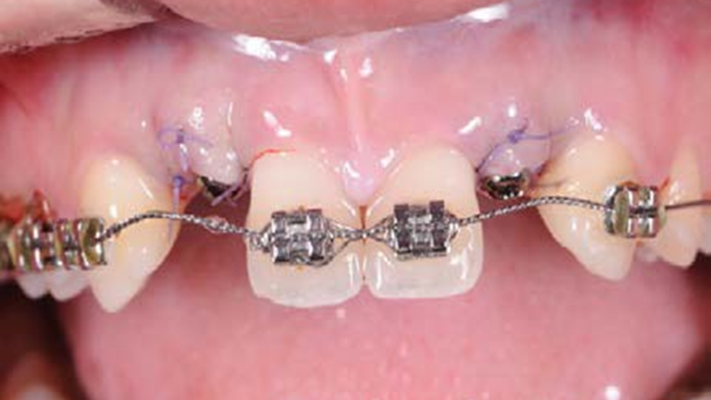

Clinical case: Patient-centered approach: treatment strategy for Root Membrane Technique & delayed implant placement

- Courtesy of Dr. Yoshiharu Hayashi, Japan -

Socket Shield Technique, anterior esthetics, maxillary anterior, esthetic, esthetics, delayed implant placement, socket preservation, AnyRidge, Root Membrane Kit, Root Membrane Technique, Partial Extraction Therapy, PET, esthetic zone, fuse abutment, Dr. Yoshiharu Hayashi,#11,#21,#22

AnyRidge implant system, fuse abutment Root membrane kit, PET Kit